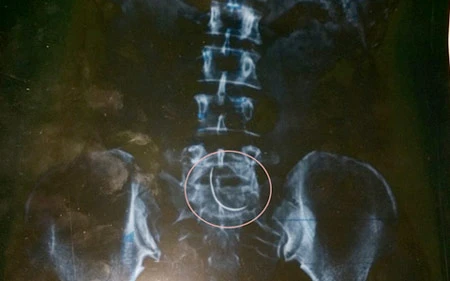

Chiếc kim (trong khoanh tròn) bị bỏ quên 9 năm trong bụng bệnh nhân. Ảnh:  Kinhdoanhnet

Trước đó, tháng 10-2005, chị Nguyễn Thị Hòa (xã Xuân Lộc, huyện Can Lộc) mang bầu được sáu tháng thì bị u tử cung, được gia đình đưa đến BV Đa khoa huyện Can Lộc cấp cứu. Tại đây, chị Hòa được êkíp gồm BS Ngọc, BS Chung cùng các nhân viên của bệnh viện mổ và cứu sống được chị Hòa. Thời gian qua, chị Hòa hay bị đau vùng bụng, lưng và không tiếp tục mang thai được. Đến đầu tháng 11-2014, chị Hòa đến BV chụp X-quang, phát hiện ở khu vực vết mổ cũ còn quên chiếc kim khâu cong và dài 3-5 cm.